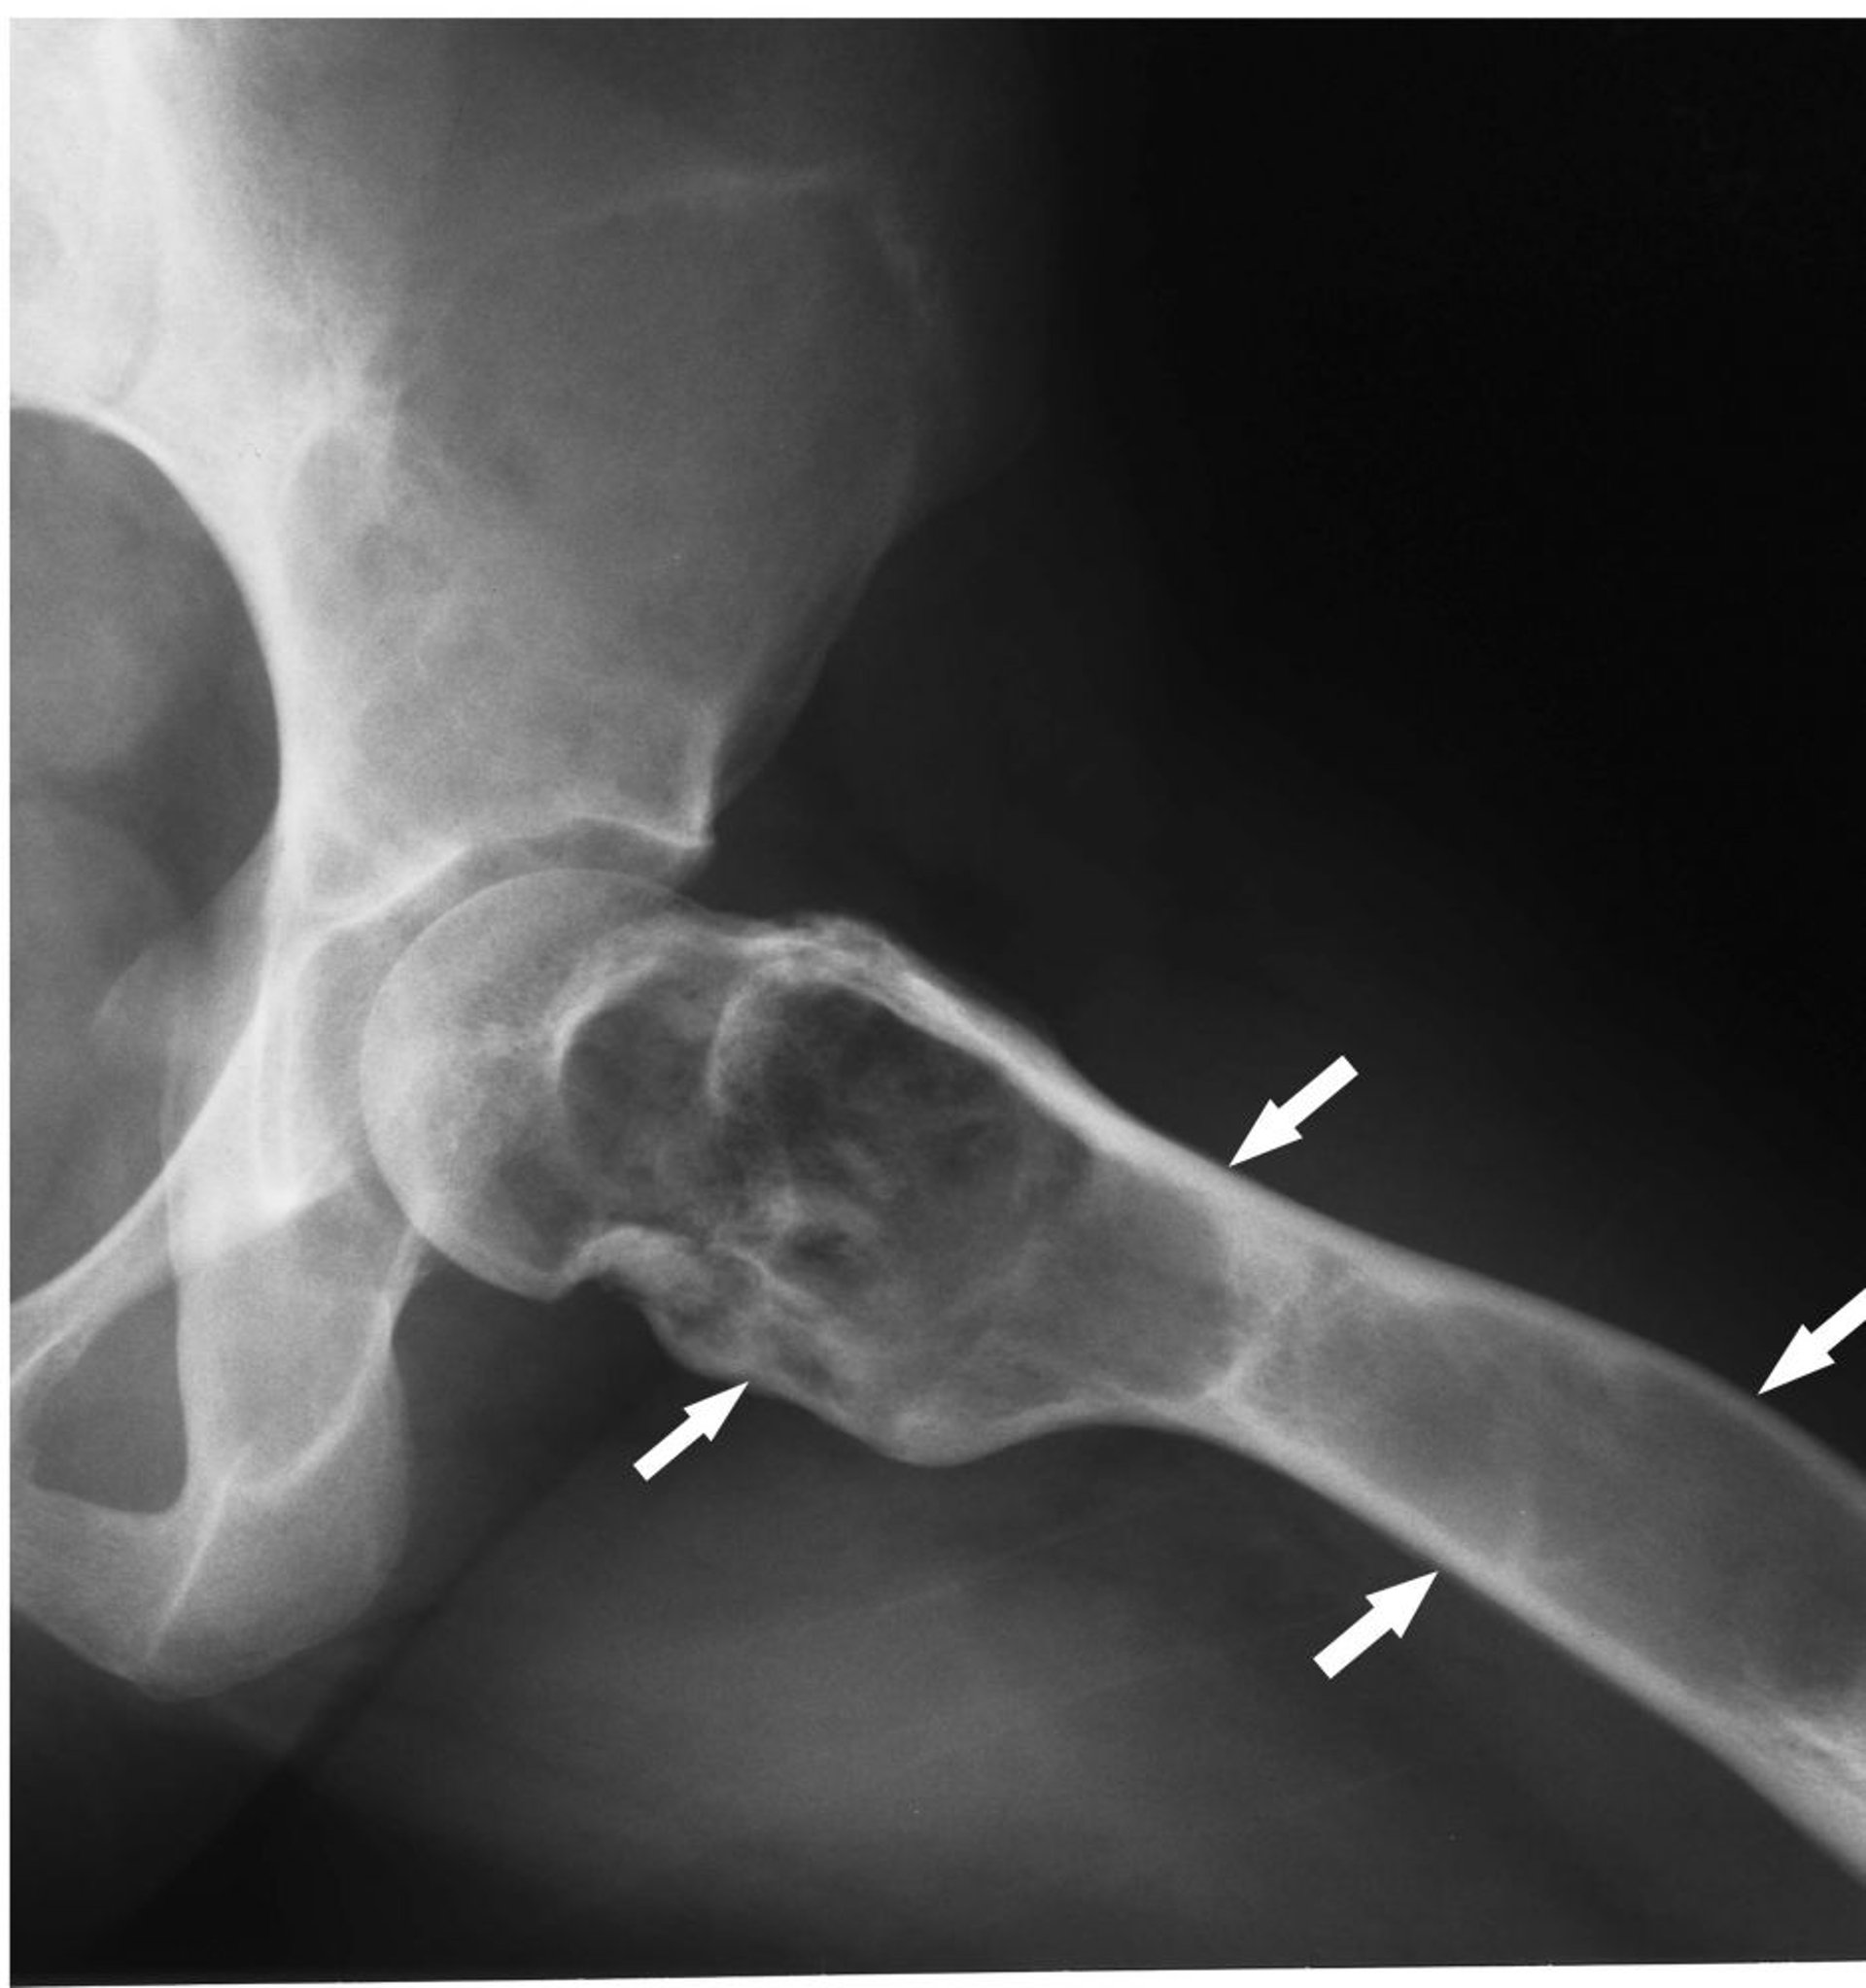

Dysplasie fibreuse

Cette radiographie de la hanche montre une dysplasie fibreuse (flèches) avec expansion corticale et matrice en verre dépoli.

Image courtoisie de Michael J. Joyce, MD, and Hakan Ilaslan, MD.